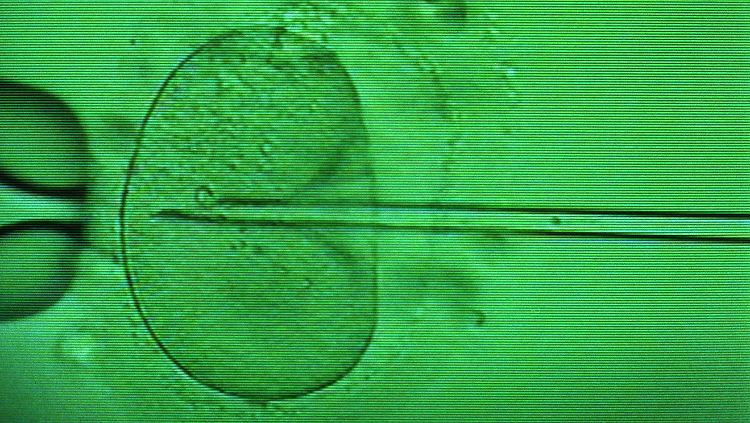

Künstliche Befruchtung.

(Foto: picture-alliance/ dpa/dpaweb)